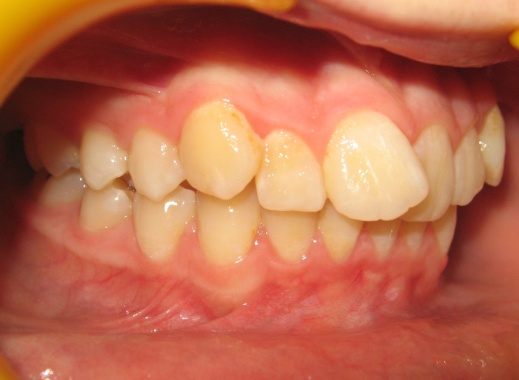

1 - Arcades dentaires avant-après

Les photos montrent un encombrement dentaire important associé à une classe II dentaire. Les extractions de prémolaires ont été décidées non seulement pour créer la place nécessaire à l’alignement, mais aussi pour corriger le décalage de classe II. Le résultat final illustre qu’un plan de traitement bien réfléchi peut répondre simultanément aux impératifs fonctionnels et esthétiques, sans compromettre l’harmonie faciale.